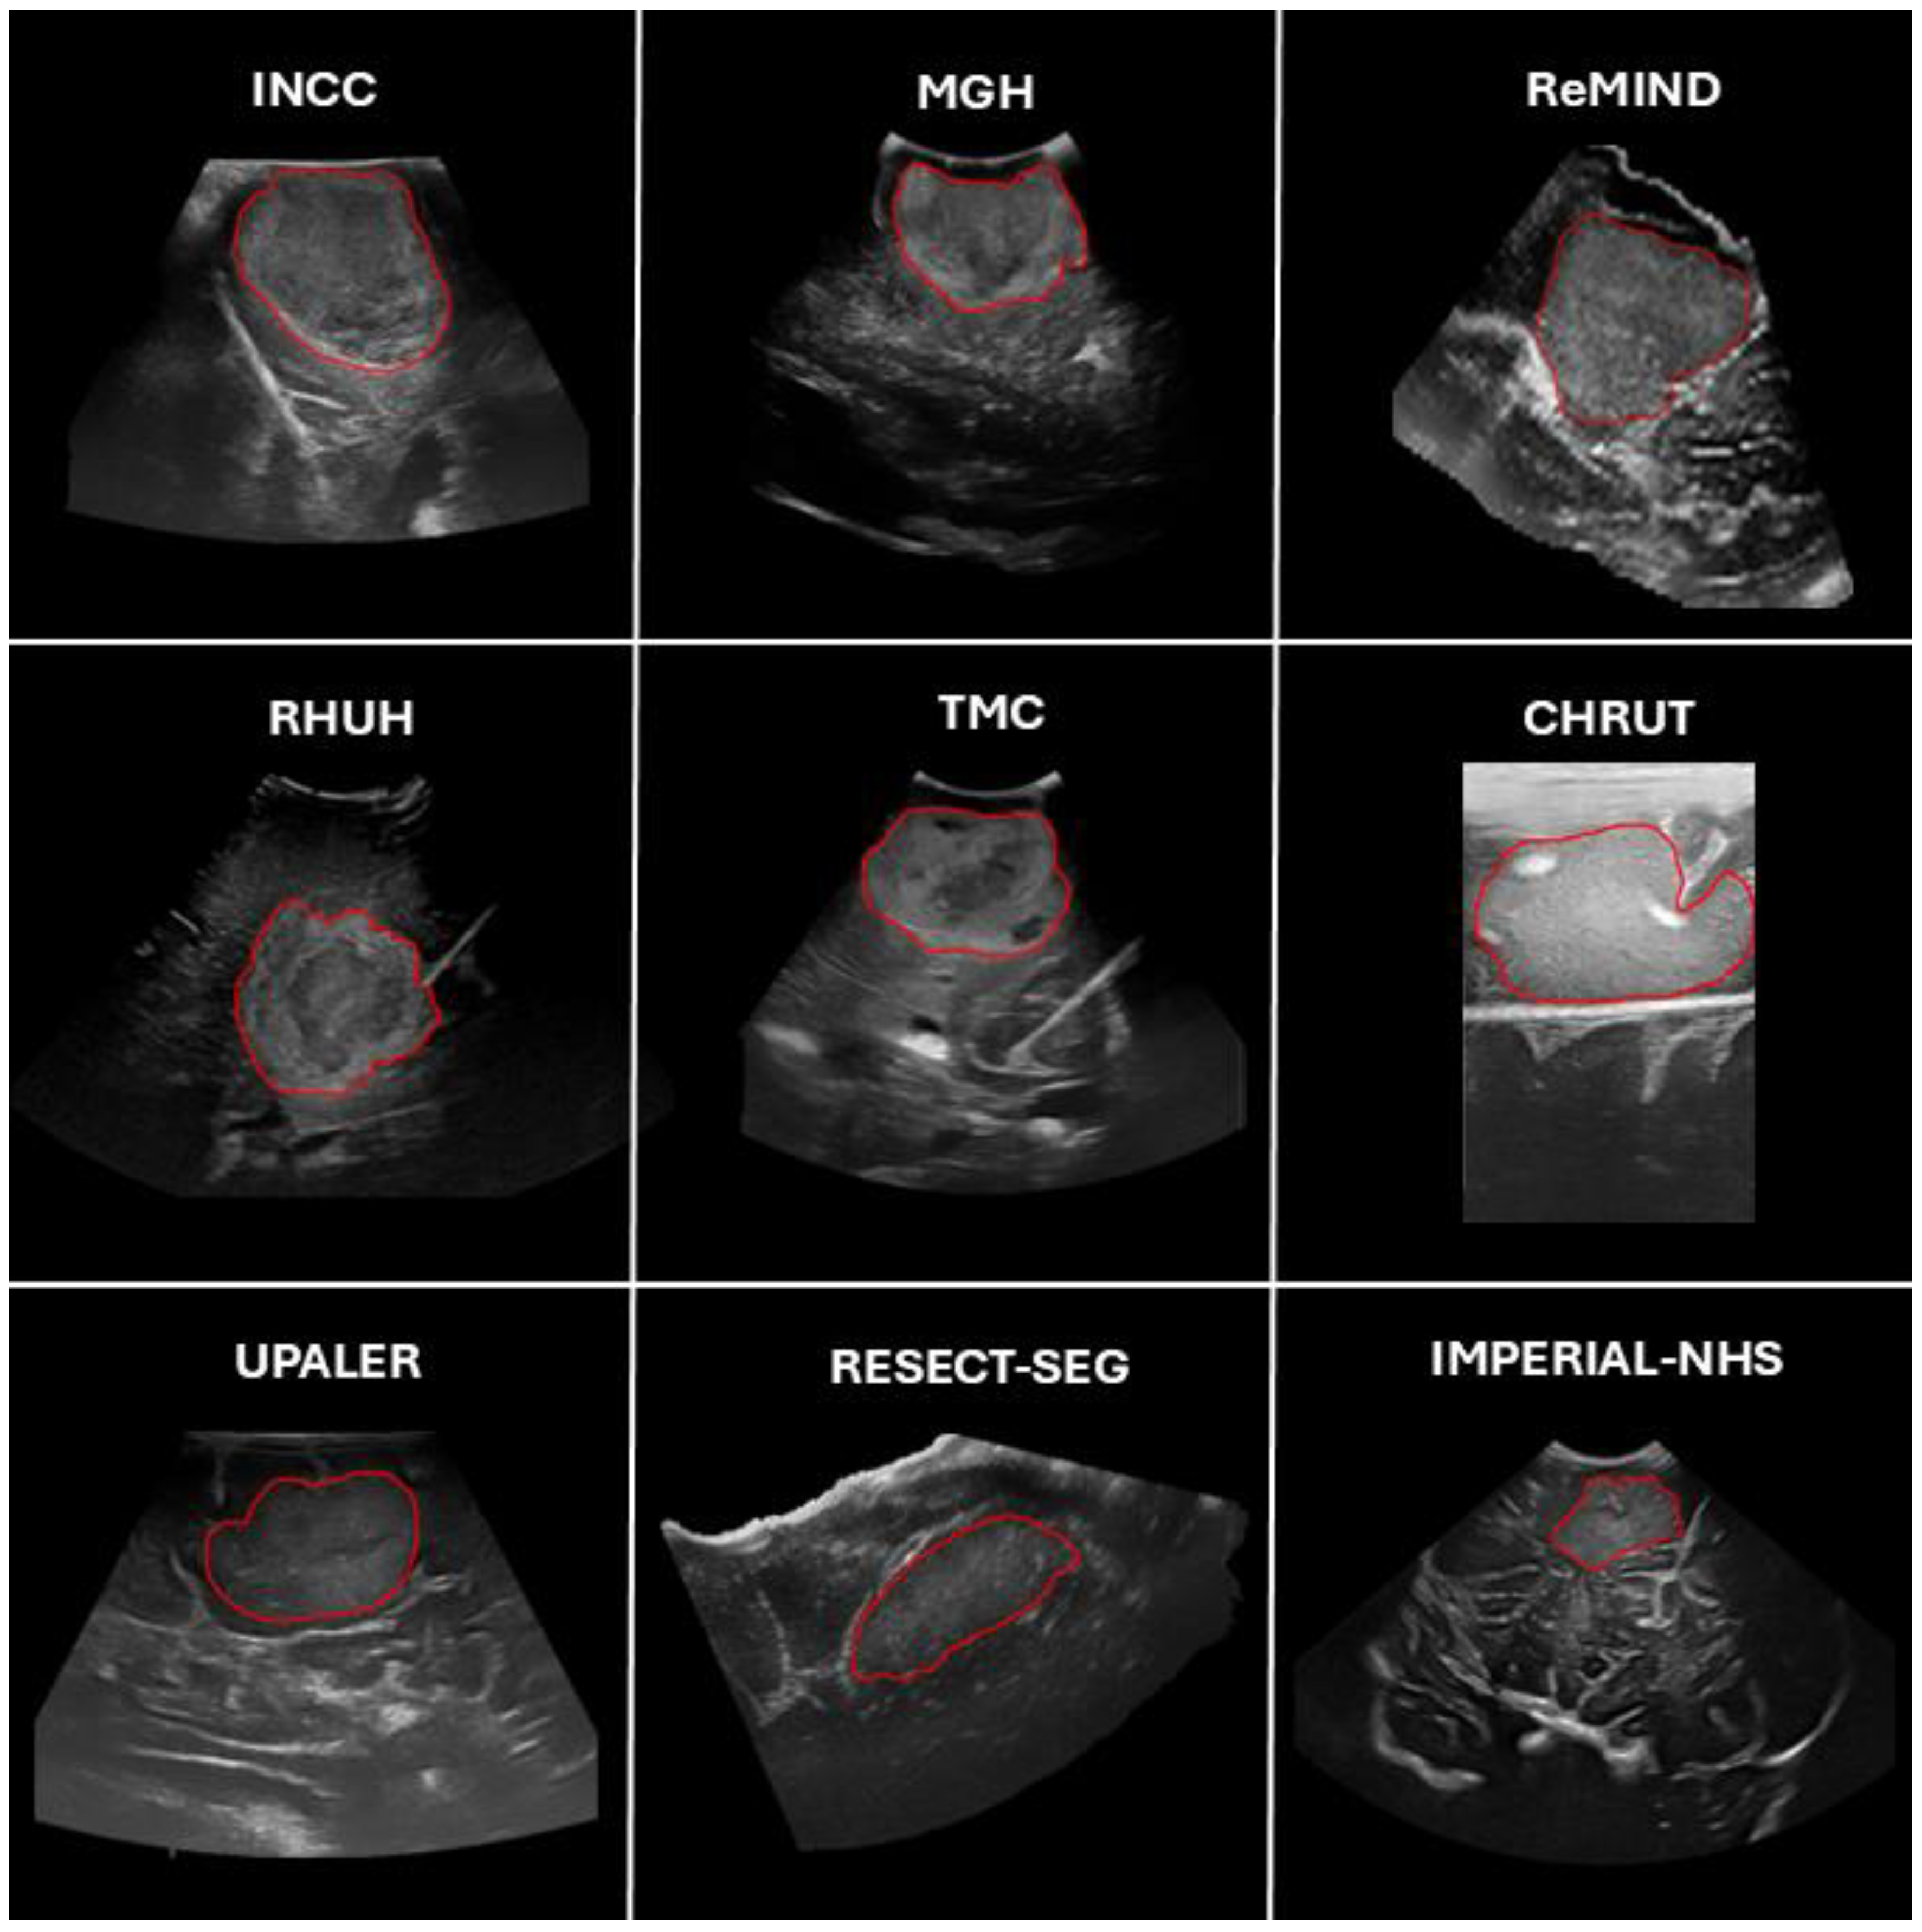

Figure 2.

Representative examples of patients from the different datasets and centers included in the study. Tumor segmentations, considered the ground truth, are highlighted with red contours.